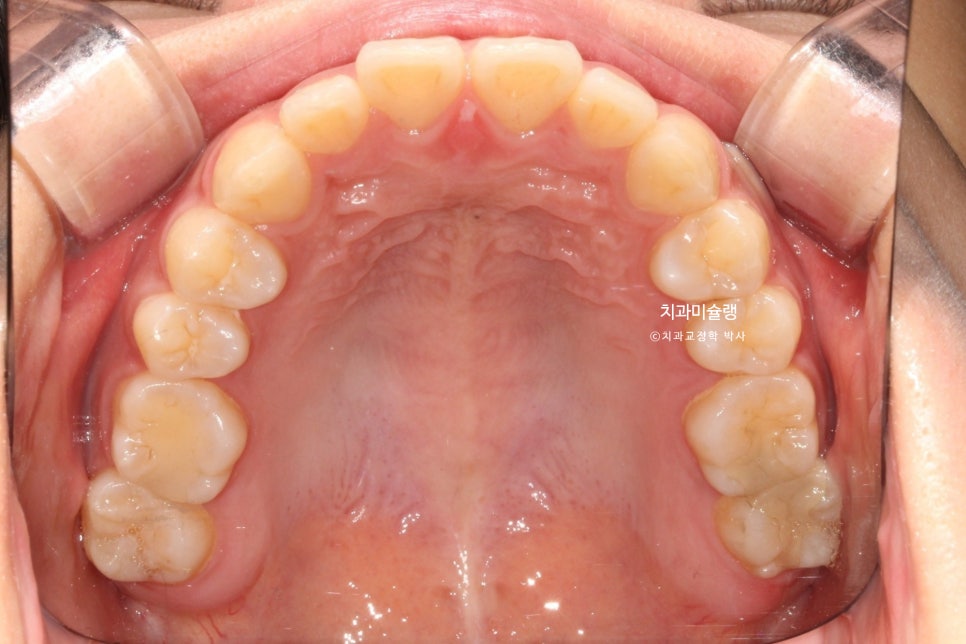

중심선 불일치, 앞니 벌어짐이 보입니다.

위 앞니가 뻗쳐있고 튀어나와있네요.

작은어금니를 발치할 정도의 돌출은 아니라 비발치 돌출입 교정 권유드렸습니다.

더불어 아래턱을 자가회전 시켜 하관을 짧게 만들고, 무턱처럼 보이는 턱끝도 개선하기 위해 상악 전체치열 후방이동과 동시에 함입도 하기로 합니다.